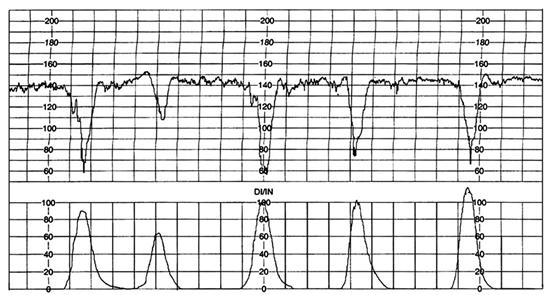

Trasee CTG la travalii declansate sau dirijate cu ocitocina sau prostaglandine

Travaliul declansat si/sau dirijat cu prostaglandine , respectiv ocitocina, prezinta particularitatea riscului hiperstimularii uterine cu hipertonie si hiperkinezie. Sindromul de suprastimulare se defineste ca aparitia tahisistoliei sau a hipertoniei asociata cu tahicardie fetala, deceleratii lungi sau pierderea variabilitatii bataie cu bataie. Aceste efecte secundare ale medicatiei utilizate pentru declansarea si dirijarea travaliului, creeaza conditii defavorabile intrauterine, prin scaderea fluxului placentar, cu posibilitatea aparitiei suferintei fetale .In continuare sunt prezentate cinci trasee cardiotocografice ale unor travalii declansate cu prostaglandine .

Fig. nr. 313. Pacienta M.M. - hiperkinezie la dilatatia de 5 cm, nastere pe cale vaginala, nou-nascut prematur, 2350 gr., Apgar 8/1' ( 1 cm / min )

Fig. nr. 314. Pacienta C.A., hiperkinezie uterina, nastere pe cale vaginala, nou-nascut 3600 gr, Apgar 9/1' (1 cm / min)

Fig.nr.315. Pacienta A.G. - hiperkinezie la dilatatia de 3 cm, nastere pe cale vagi-nala, nou-nascut de 3600 gr., Apgar 10/1', pH din cordonul ombilical 7,209 (1 cm / min)

Fig. nr. . Pacienta U.M. - hiperkinezie la dilatatie de 4 cm, nastere pe cale vaginala, nou-nascut de 2900 gr., Apgar 9/1', pH din cordonul ombilical 7,209.( 1 cm / min)

Fig. nr. 3 Pacienta S.B. - sindrom de hiperstimulare (hiperkinezie si deceleratii variabile prelungite ale ritmului cardiac fetal) la 4 cm dilatatie - operatie cezariana , nou nascut postmatur, 3750 gr., Apgar 9/1' si 10/5' (1 cm / min)